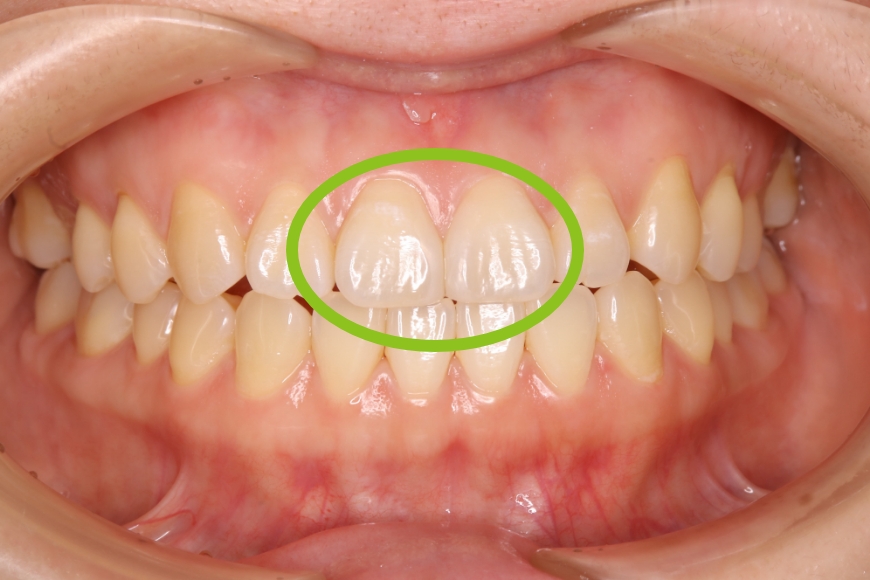

38歳女性 前歯正中離開に対するダイレクトボンディング

治療前

治療後

治療内容 前歯の「すきっ歯」が気になるとのことで来院されました。

矯正治療、セラミック治療、ダイレクトボンディング治療を提案しました。治療期間の短縮と歯質の保存を優先し、ダイレクトボンディングによる治療を選択されました。

ラバーダム防湿下で専用のコンポジットレジンを段階的に充填し形態・色調を再現しました。(歯を削っていません)

治療回数 通院回数:1回

治療費用(総額)

88,000

(1本44,000円×2本分。治療時の金額であり、時期や手法により異なる場合があります。)

副作用・リスク ・歯ぎしりや過度の咬合力により破折する可能性があります。

・時間の経過とともにわずかな着色や摩耗が生じるため、長期的には再調整や再充填が必要になる場合があります。